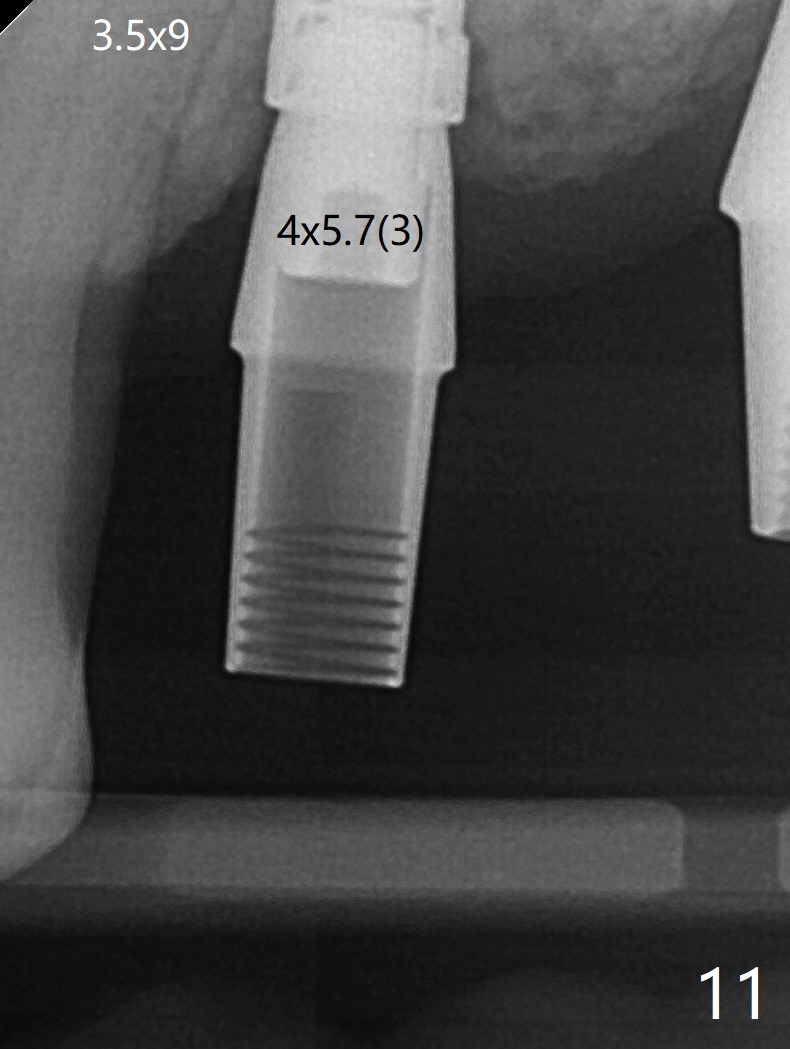

The patient returns for #4 extraction and immediate implant the 1st day clinic reopening after coronavirus lockdown. To reuse autogenous bone for #4 buccal gap closure, delayed implants are also placed at #13 and 14. It is much easier to determine the placement level of the immediate implant (open socket) with guide than that of the delayed ones (flapless) clinically. Immediate postop CT is taken for implant placement level confirmation (Fig.1-3). In fact the autogneous bone is too soft to be packed into #4 socket gaps. It has to be mixed with allograft to be packable. There is oozing when #14 healing abutment is placed. The hemorrhage is severe 4 days postop. The healing abutment is replaced by a healing screw. Hemostasis is achieved when the access is closed with GEM Cap and 4-0 Chromic gut suture. The patient will return for #3 extraction and socket preservation 1 month postop (Fig.4). To prevent postop hemorrhage, a cemented or temporary abutment will be placed at #4 before anesthesia, while .5 or 1.0 cc Augma bone will be placed at #3, covered with collagen plug and acrylic. In fact he cancels the appointment once because of symptom relief and will return 2 months postop. Sticky bone (Fig.5 *) and PRF is used at #3 for hemostasis, while a 5x5.7(3) mm pair (final) abutment is used to hold acrylic dressing in place. The latter remains in place with good oral hygiene 1 month postop (Fig.6 A: abutment). When the acrylic dressing is removed, the socket heals (Fig.7 K: the gingiva between the buccal and palatal sockets when the tooth was removed). The patient returns for impression 4.5 months postop. When the 5x5.7(3) mm abutment at #4 is reseated after cleaning, there is no horizontal gap between the abutment and implant in BW (Fig.8), while there is in PA (Fig.9). When a smaller abutment is seated (Fig.10), there appears to be a horizontal gap, whereas there is no vertical one. The situation is the same with #13 (Fig.11,12). The common denominator is 3.5 mm implant. With suspicion, BW is taken for the implant at #4 immediately before cementation (Fig.13). It appears that the abutment is most likely seated completely. There is no bone loss or screw loosening 4 months post cementation (Fig.14,15). One month later the patient agrees to have 3 lower implants to replace RPD.